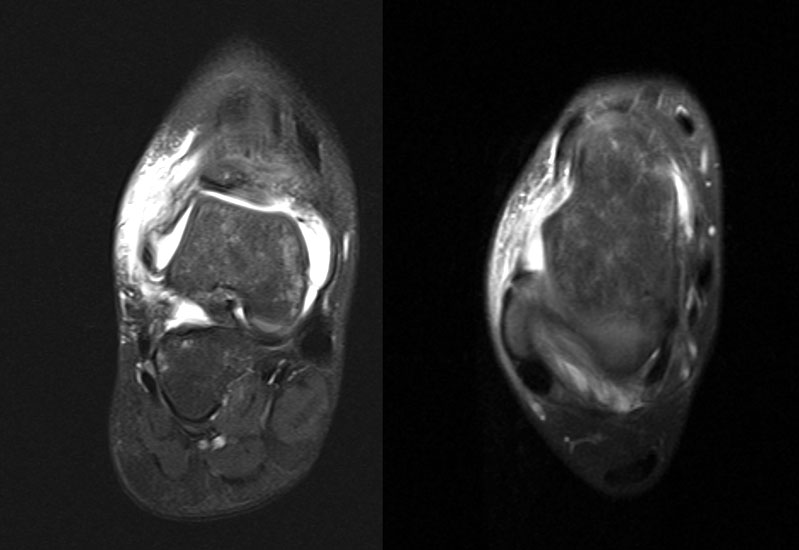

Schnittbildverfahren sind immer dann indiziert, wenn der Verdacht auf Begleitverletzungen besteht, das Schmerzniveau inadäquat hoch ist, oder die akuten Beschwerden innerhalb einer Woche nicht weitgehend abgeklungen sind 31 (Abb. 4-6).